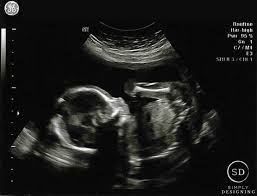

Fetal yoke sac as seen on ultrasound at eight weeks. Below are scan pictures taken during the early weeks of pregnancy. Ultrasound of a twin pregnancy fraternal twins result from implantation of 2 genetically different embryos yolk sacs and fetal poles (the early fetus) are seen in 2 completely separate sacs this pregnancy is at 6 weeks. Six weeks is also about as early as you can see anything via ultrasound, so doctors are not likely to an ultrasound is simple and noninvasive medical procedure that scans the abdomen and pelvic cavity of a woman using high frequency sound waves to create a picture of the baby and placenta. Here, learn what to expect and whether 3d and 4d scans are safe.

An ultrasound may be performed for a variety of reasons, but looking at a baby in the womb is the most common reason. Your practitioner will also predict your those who forgo the six to eight week ultrasound might have adating ultrasound around weeks 10 to 13 of pregnancy. Here, learn what to expect and whether 3d and 4d scans are safe. A twin ultrasound at 6 weeks needs to be done vaginally to detect twins this early in your pregnancy. Unfortunately, seeing no yolk sac at 6 weeks can also be a sign of miscarriage. Details on 6th week pregnancy symptoms & baby development >>. But that you so much for all the support ❤ you guys are amazing! It shows my uterus, the dark shape in the middle.

Twin pregnancy belly week by week + symptoms & ultrasounds. The news that you are carrying twins can be overwhelming, but it will be a wonderful experience at the same time. 10 weeks 4 days posted by: 6 week ultrasound | ivf journey 2018. Life and love in the petri dish 7 week ultrasound. A twin ultrasound at 6 weeks needs to be done vaginally to detect twins this early in your pregnancy. Discover the perfect ultrasound pictures of baby for your project! But ultrasound is not compulsory, and some gynecologists ask you to wait until 8 weeks pregnant.

Picture of ultrasound at 5 to 6 weeks of pregnancy. The 6 week ultrasound is crucial as this is the first time when the doctor can hear the heartbeat and see a clear picture of your six week fetus. 6 weeks ultrasound twinspictures will also confirm that you are. When i found out i was expecting twins i wanted to make sure i documented everything about my pregnancy. Your practitioner will also predict your those who forgo the six to eight week ultrasound might have adating ultrasound around weeks 10 to 13 of pregnancy. It shows my uterus, the dark shape in the middle. #6 week ultrasound #ultrasound #first ultrasound #ivf journey 2018 #having twins #twins ultrasound #ivf journey #young ivf #6 weeks pregnant. At six weeks' gestation, it's possible to see the baby's heartbeat. Check out hundreds of amazing twin ultrasound images! Ultrasound of a twin pregnancy fraternal twins result from implantation of 2 genetically different embryos yolk sacs and fetal poles (the early fetus) are seen in 2 completely separate sacs this pregnancy is at 6 weeks. At 6 week ultrasound, the embryo is barely 0.25 inches, which is the size of a sweet pea. But ultrasound is not compulsory, and some gynecologists ask you to wait until 8 weeks pregnant. An ultrasound with twins will show the babies as two dark spots in the uterus.